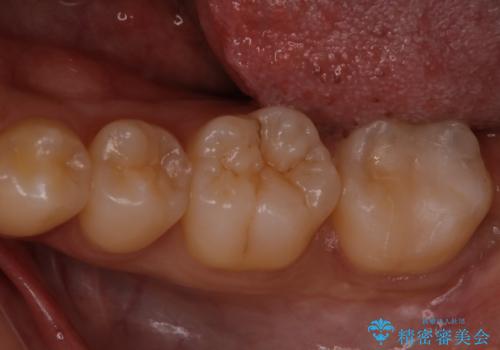

白く目立たないものでの治療をご希望されたため、セラミックインレーでの治療となりました。

適合の良いセラミックインレーで修復することで見た目の綺麗さを保ったまま治療することができます。